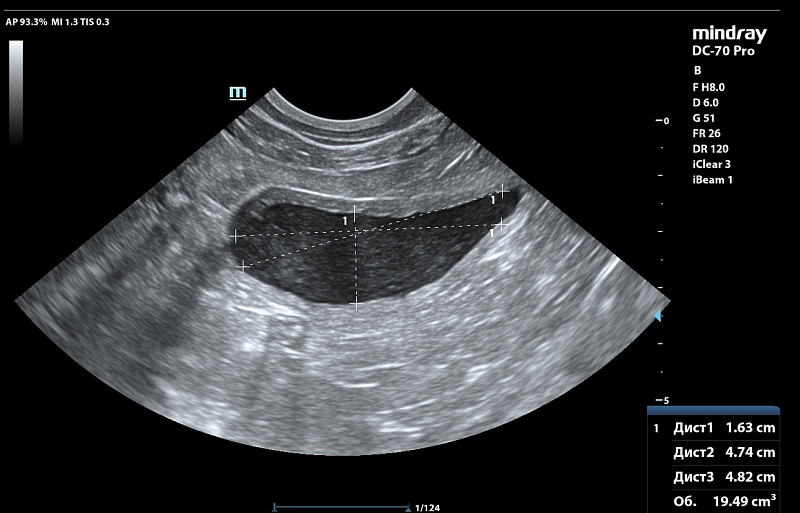

Здравствуйте! У абиссинской кошки, она астматик почти всю жизнь с дества на ингаляциях.Ей около 12 лет. На натуральном питании (бедро индейки, куринная шейка, сердечки индейки и свиной язык (только он в вареном виде, 2 года назад на таком питании все было в норме в анализах биохимияя и анализ мочи, но последние 4 мес я увеличила процент мяса в отношении, давая его 3 раза в неделю вместо языка в котором меньше фосфора)). 1.5 мес назад заметила запах у мочи и я решила подавтаь кантарен и в конце курса 8 кап на 8 кг она нагадила на пол и заметили что и запах пошел у мочи и мутная уже. Писала она 2 раза в день по многу. Крови не было. Резко стала пить больше воды по чашке дней 10 до амоксиклав. Вес не теряла ни 100 гр. Решили раз ничего серьезного подавать фураданин 1/2 таб 2 раза в день. Сильный запах почти сразу ушел. но мутность еще была, на 6 день лечения она покакала частично с поносом и тужилась и хотела остатки стула выдавить каках, стали вытирать ее и тогда словно спазм и она сделала 3 коротких метки и потом легла и пошла кровь. Крови было много, шла из мочевого канала часа три пока кошку не заперли в переноскеи в покое отсановилась уже после вет клиники. Врач хирург сказал что кажется много, а для ее веса немного крови. Ночью в ветклинике сделали узи почек и мочевого, сказали есть возврастные изменения ( они были и 5 лет назад и почки работали ок при этом), но ничего прям критичного по почкам по узи, смотреть анализы, мочевой стенка 0.3 мм вместо 0.1мм в прошлом когда кошка была 5 кг еще худее и здорова.

Сдали анализы после 8 ч голода ( не давали фурадонин 13 ч до аналиаза) Все анализы сдано 8 ч голода и 13 ч после отмены фурадонина (давали до 6 дней с пропуском 1 дозы тк 1 раз дала целую таблетку и ее вырвало. Прилагаю анализы и узи со снимками. Температуры у кошки не было, в р-не 38.1.